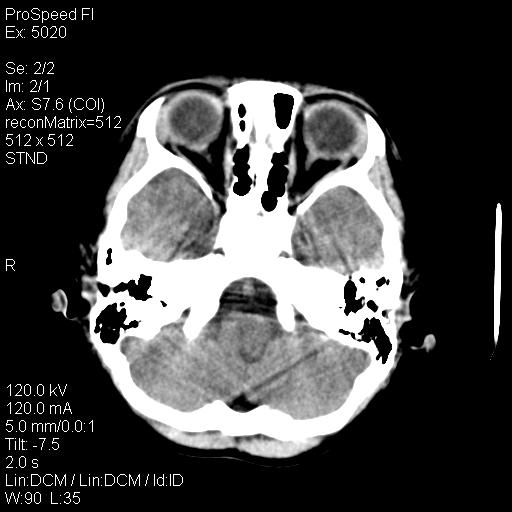

标题: PED1637:M 6Y 顶部无痛性包块两月。 [打印本页]

标题: PED1637:M 6Y 顶部无痛性包块两月。

2、颅骨局部缺失,边缘光滑、整齐

颅骨的病损表现为内外颅骨板层不规则的锋利的破坏,形成“斜边缘”,有一定的特点

颅骨为好发部位,生长缓慢,常位于顶骨、枕骨及颞骨,表现为颅骨缺损,呈圆形或椭圆形,边界清,无硬化